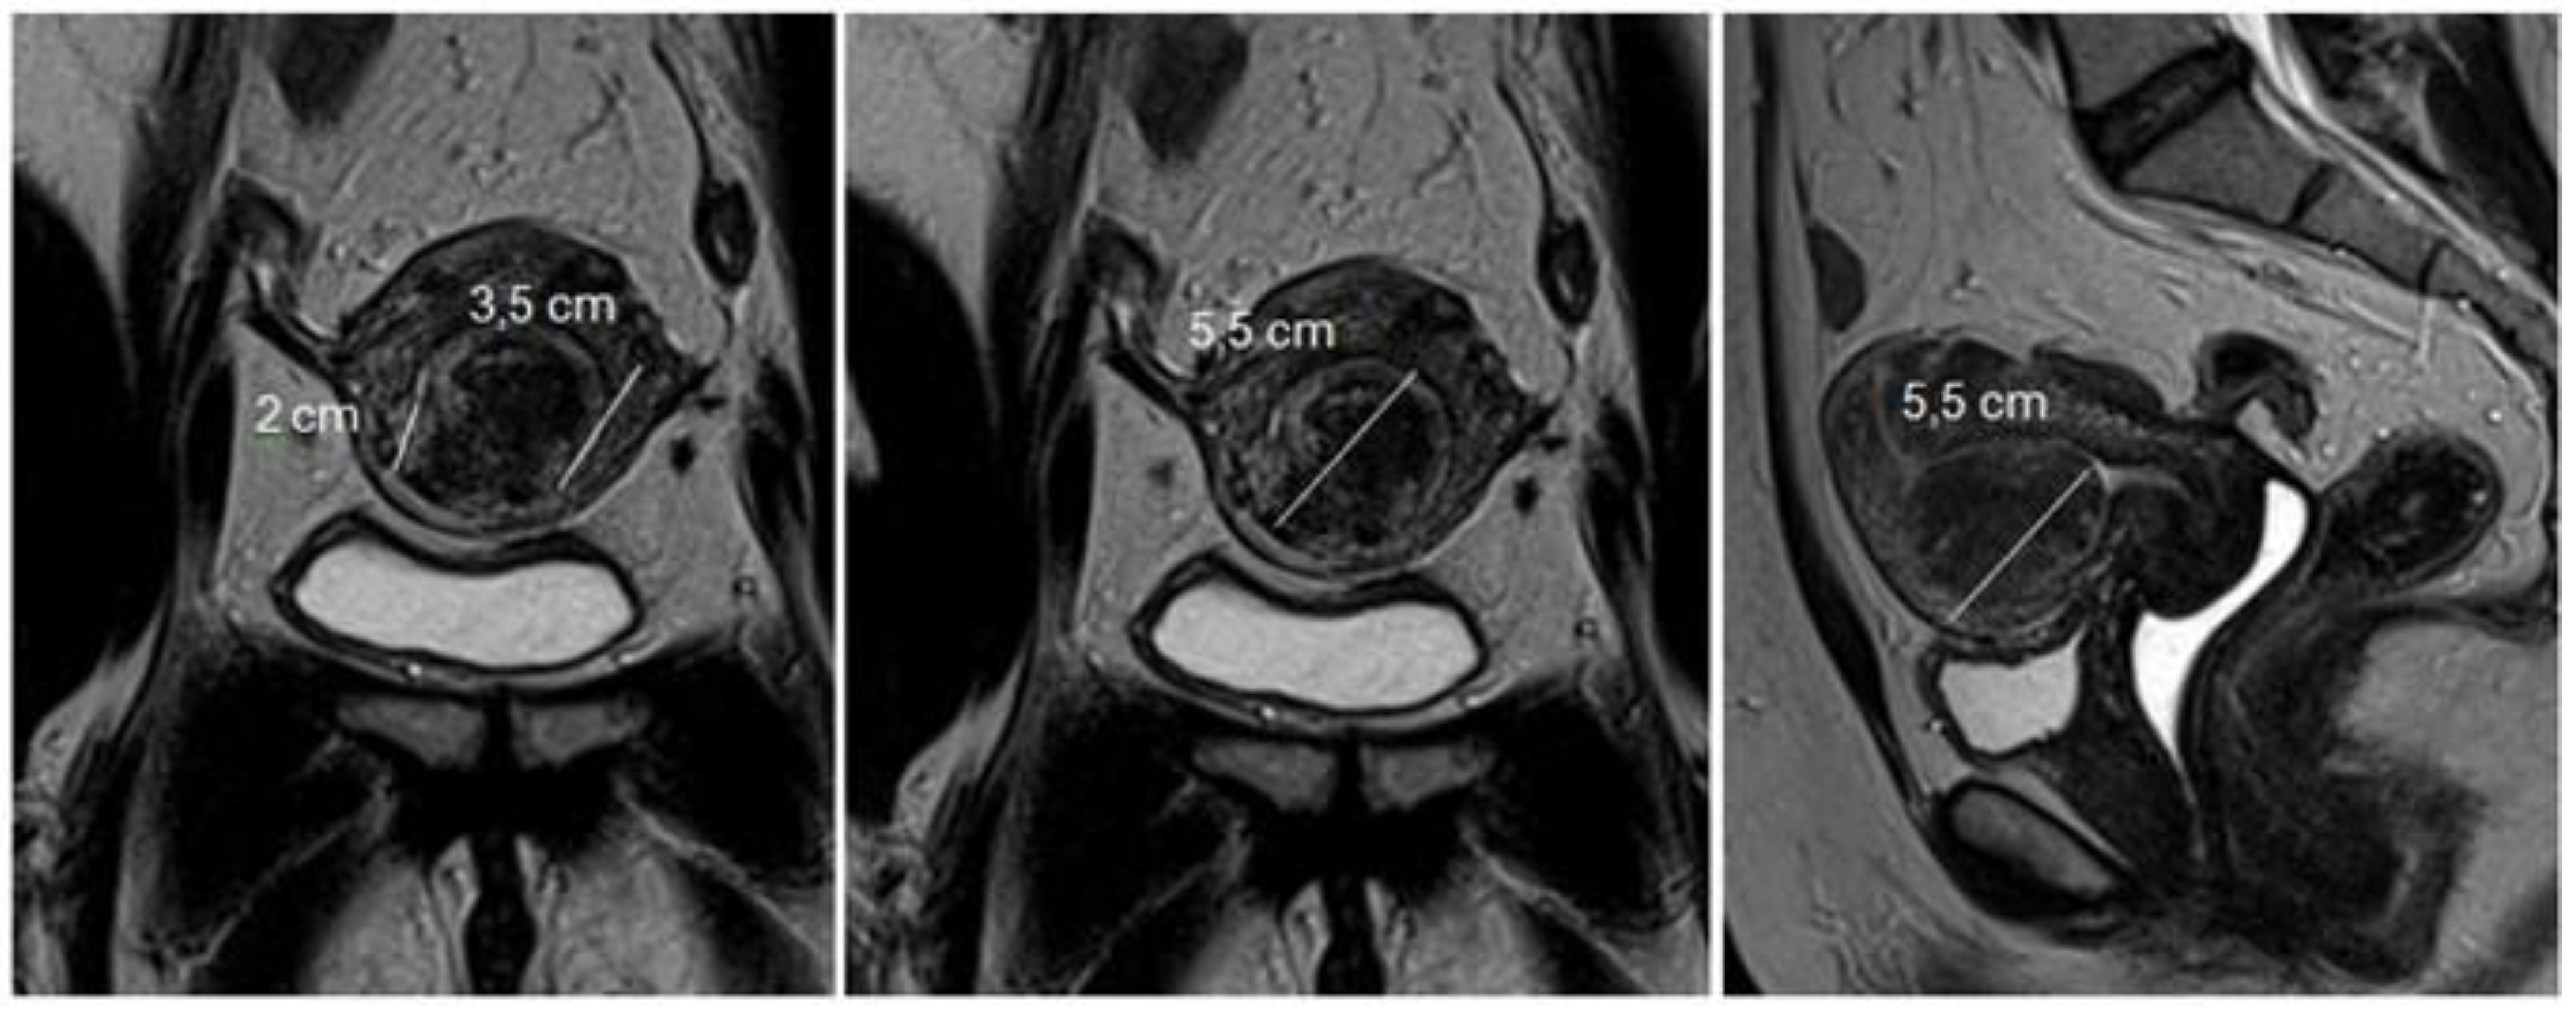

The effect of nearby fibroids, represented by a submucous fibroid with another intramural fibroid next to it, is considered. In this case, the Lasmar classification starts to consider the set as a single node, thus changing the final classification. This is due to the complexity, risk, and surgical result, since, when the myomectomy of the submucous myoma is concluded, another intramural fibroid will be found, which will probably be close to the serosa or have a subserosal component (Figure 5).

Thus, with the new classification, it will be possible to modify the surgical approach for myomectomy. In these cases, hysteroscopic myomectomy associated with laparoscopic myomectomy is indicated.

Figure 5. The effect of nearby fibroids.